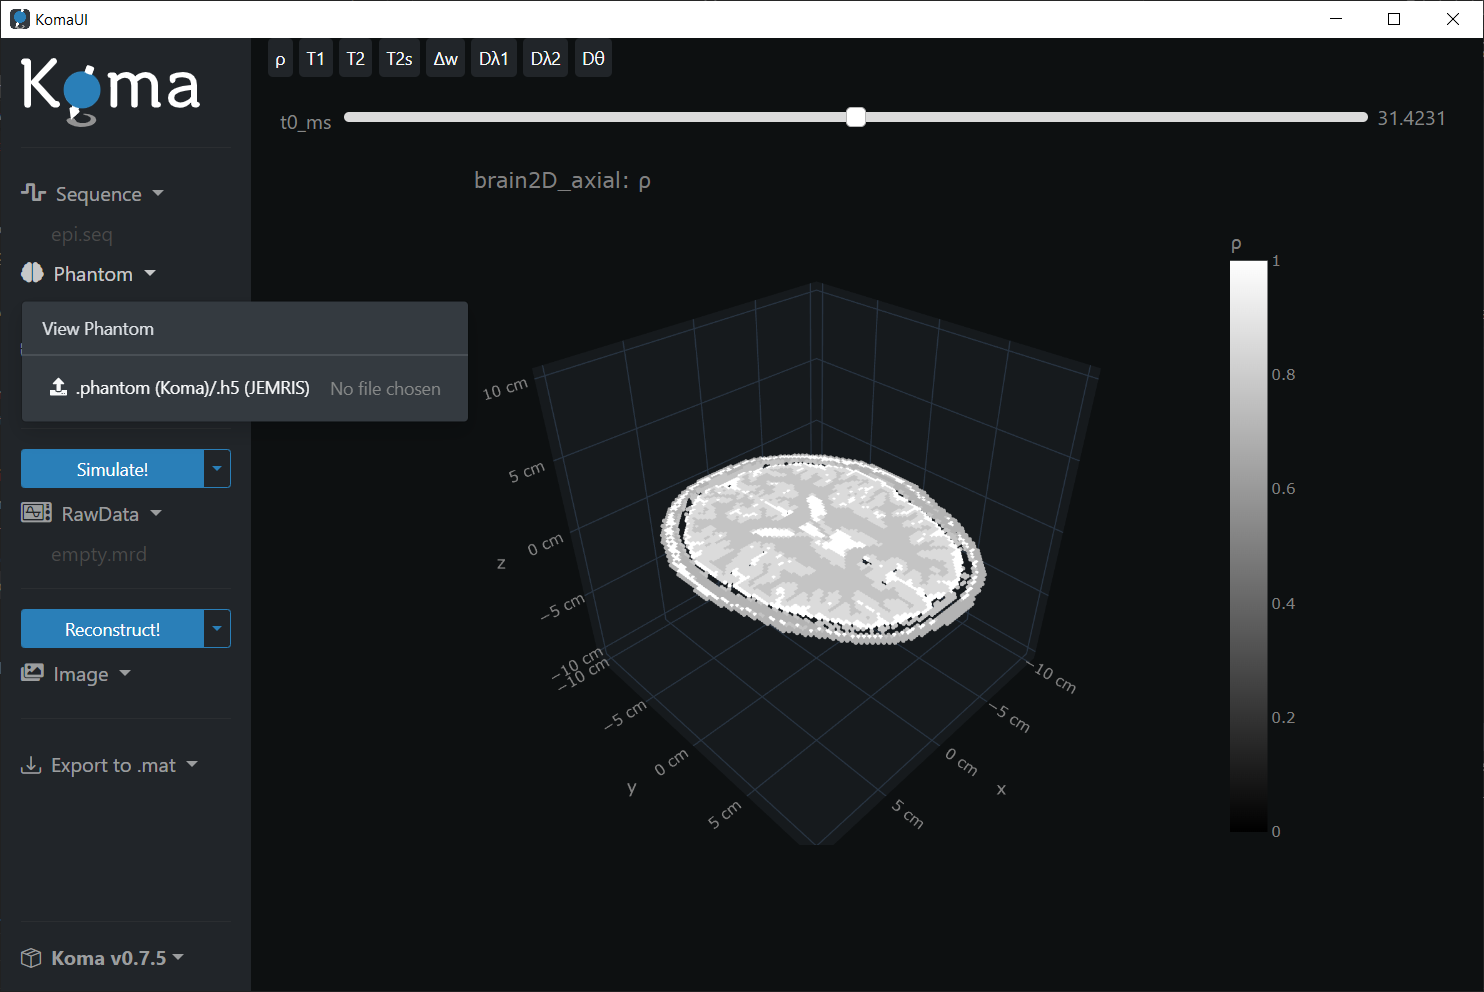

Phantom

To see the phantom already stored in RAM, simply click on the Phantom dropdown an then press the View Phantom button. The preloaded phantom is a slice of a brain:

It is also possible to load .h5 phantom files. The KomaMRI.jl has some examples stored at ~/.julia/packages/KomaMRI/<id-string>/examples/2.phantoms/. For instance, let's load the sphere_chemical_shift.h5 file:

Note that you can select different spin parameters to visualize like ρ, T1, T2, among others.